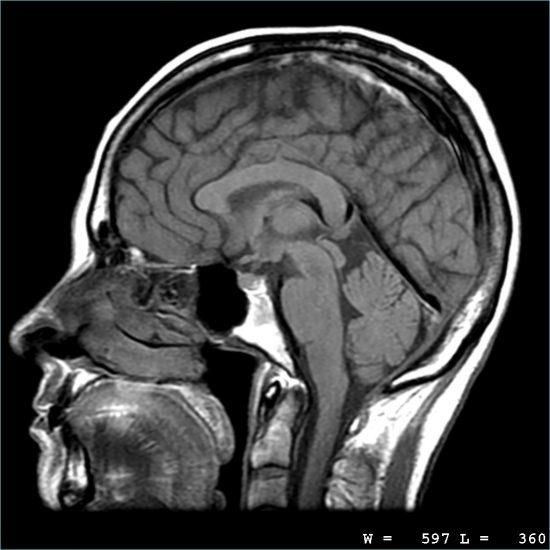

8. Chụp cộng hưởng từ (MRI)

MRI là kỹ thuật tạo hình cắt lớp sử dụng từ trường và sóng radio. Nguyên tử Hydrogen trong cơ thể dưới tác động từ trường và sóng radio, hấp thụ và phóng thích năng lượng sóng RF. Các mô cơ thể khác nhau sẽ hấp thụ và phóng thích năng lượng khác nhau. Quá trình phóng thích năng lượng được máy thu nhận, xử lý, chuyển đổi thành các tín hiệu hình ảnh. Hình ảnh MRI có độ tương phản cao, chi tiết giải phẫu tốt, khả năng tái tạo 3D, không có tác dụng phụ như X quang nên ngày càng được chỉ định rộng rãi không chỉ cho thần kinh mà còn cho nhiều lĩnh vực khác: cơ xương khớp, tim mạch, bụng…

MRI là kỹ thuật hình ảnh hiện đại, mang tính cách mạng kỹ thuật đối với y học. Cho đến nay, MRI ngày càng được sử dụng rộng rãi bởi sự chính xác, an toàn, không xâm nhập và không dùng tia X. Hình ảnh có độ phân giải cao, khảo sát đa mặt cắt, cho hình ảnh sắc nét về bộ phận cần chụp, đồng thời đánh giá được các tính chất của mô cần khảo sát.

Lợi ích của máy cộng hưởng từ:

- – Bệnh nhân không bị ảnh hưởng bởi tia xạ.

- – Bệnh nhân không bị ảnh hưởng gì về mặt sinh học.

- – Thu được hình chụp đa mặt phẳng: Mặt phẳng trán, mặt phẳng ngang, mặt phẳng dọc hay bất kỳ mặt phẳng nghiêng nào.

- – Độ phân giải mô mềm cao.

- – Hiển thị hình ảnh tốt hơn khi so với CT.

- – Chụp được mạch máu não (MRA), kể cả khi không dùng chất tương phản.

- – Là kỹ thuật hình ảnh không xâm lấn.

- – Chất tương phản tác dụng phụ rất hiếm.